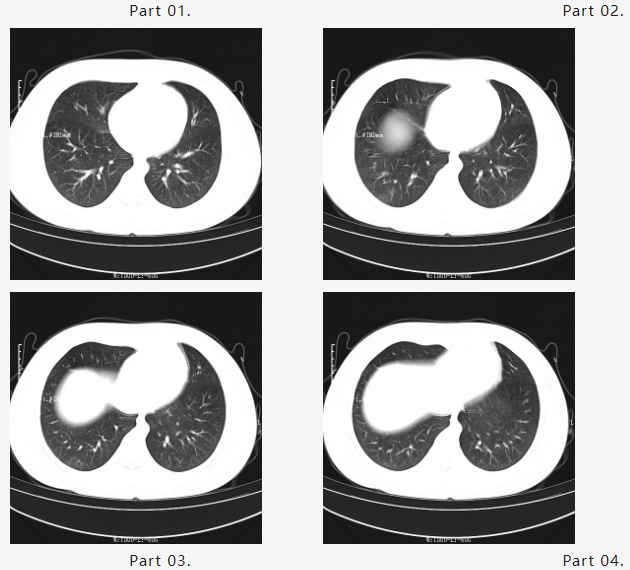

根据以往救治经验,钱源及团队开展多次对症治疗,效果并未凸显。随即再更改治疗方案,结合新病例的治疗特点及用药方式,采用量化治疗疗法。经过几天的精心治疗和护理,小毛终于转危为安,胸闷气急的症状逐渐消失,肺从“一片白茫茫”变为“一丝一缕的白”症状明显好转,复查了第一次胸部CT,结果显示如下:

在大家的不懈努力下,短时间内“白肺”明显吸收好转。马博激动又兴奋地告知大家这个好消息,大家不约而同打开小毛胸部CT片反复阅览,均露出久违的笑容……

为进一步观察病情变化,马博建议小毛母亲继续住院行巩固支持治疗,终于,在大家共同努力下迎来了出院前最后一次复查胸部CT,结果如下:

一段时间后,小毛“白肺”已经消退,肺呼吸功能完全恢复,取得非常满意的治疗效果,随即出院。